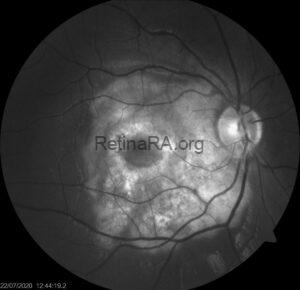

Goldmann-Favre Syndrome

A 24-year-old female patient presented to our clinic with complaints of decreased vision and nyctalopia. [...]